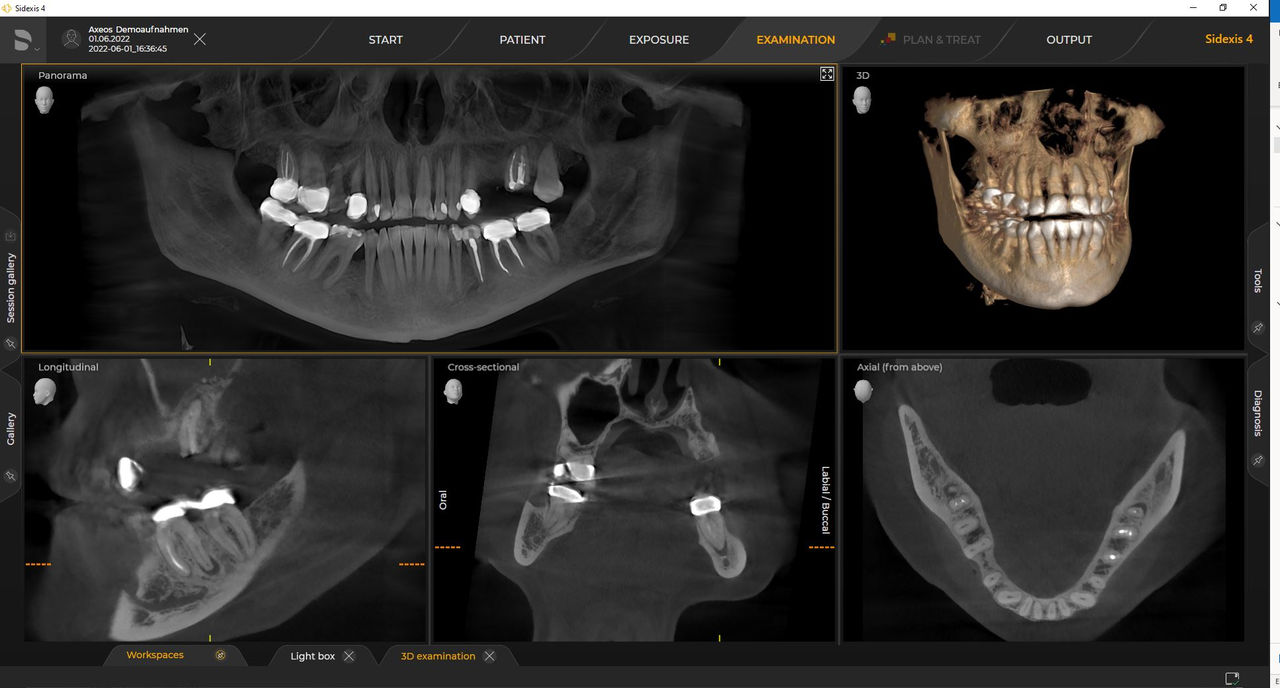

Los numerosos tamaños de volumen garantizan la flexibilidad en la práctica diaria. Examine un área precisa o evalúe la dentición completa, lo que incluye las ATM

Las unidades 3D de Dentsply Sirona funcionan exclusivamente con Sidexis 4. Sin embargo, la migración de datos de Sidexis XG a Sidexis 4 es muy fácil. Sidexis 4 permite una experiencia digital completa con las últimas herramientas.